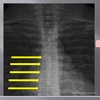

AP THORACIC LANDMARKS A-P thoracic

junction of the lamina

102

A-P thoracic

pedicle shadows

103

vertebral waist

104

A-P thoracic view

inferior endplate tips

105

superior endplate tips

106

disc spaces

LATERAL THORACIC LANDMARKS lateral thoracic view

108

Lateral thoracic view

endplate tips